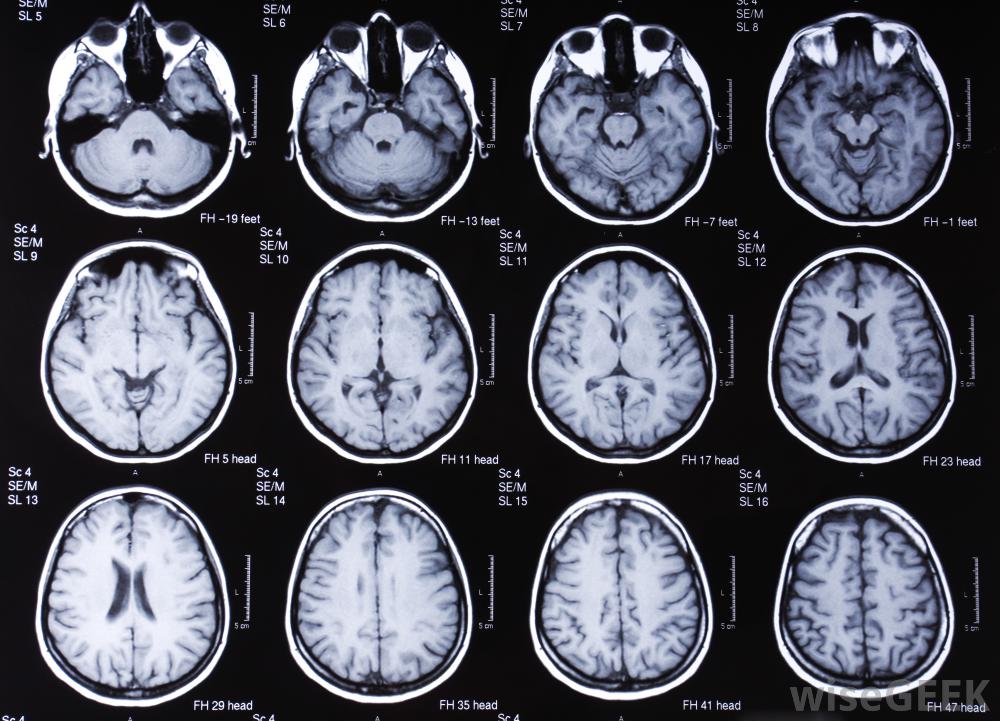

核磁共振成像(MRI)和磁共振成像(MRA)都能提供高分辨率的图像,对患者的风险很小。在MRI研究中,病人进入一个装有强力磁铁的管子,用来收集体内的一系列无创图像。这是在高分辨率下完成的,而且不受辐射的影响。磁共振成像可以对身体的任何部位进行,有些可能需要使用对比材料来突出显示病人体内的某些结构全身核磁共振扫描提供从头到脚的成像,而其他的扫描可以集中在感兴趣的区域,比如膝盖受伤或疑似的腹部癌。

核磁共振成像机利用磁场和无线电波来生成内脏和骨骼结构的图像病人可能需要核磁共振成像和磁共振成像来收集有关健康状况的信息,根据问题的性质和医生的建议。这些扫描可在诊断阶段用于收集有关患者体内发生的情况的信息。它们也可用于跟踪监测愈合进度。医生可以比较新的和旧的研究,以确定患者的病情对治疗有反应并检查并发症。

一台MRI机器。MRI和MRA的经验研究非常相似。在这两种情况下,患者都需要躺下来,在机器内尽可能保持静止。在病人感到幽闭恐怖症的情况下,开放式机器可以提供更多的舒适感,而较旧的封闭式机器可能会给一些患者带来压力在MRI和MRA扫描过程中,医护人员可能会为患者提供带有音乐和其他干扰的耳机,以及紧急停止按钮,以便在极度不适的情况下使用。